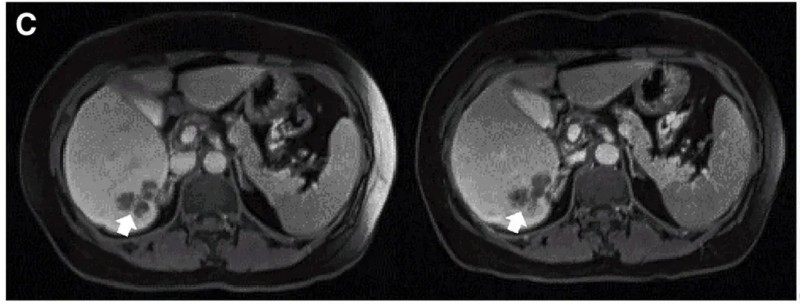

另一例P10患者:在接受DL4剂量CEA CAR-T治疗后,MRI证实肝内一处病灶缩小。下图展示了CAR-T治疗前(左图)、治疗4周后(右图)的MRI对比。

▲图源“Molecular Therapy”,版权归原作者所有,如无意中侵犯了知识产权,请联系我们删除